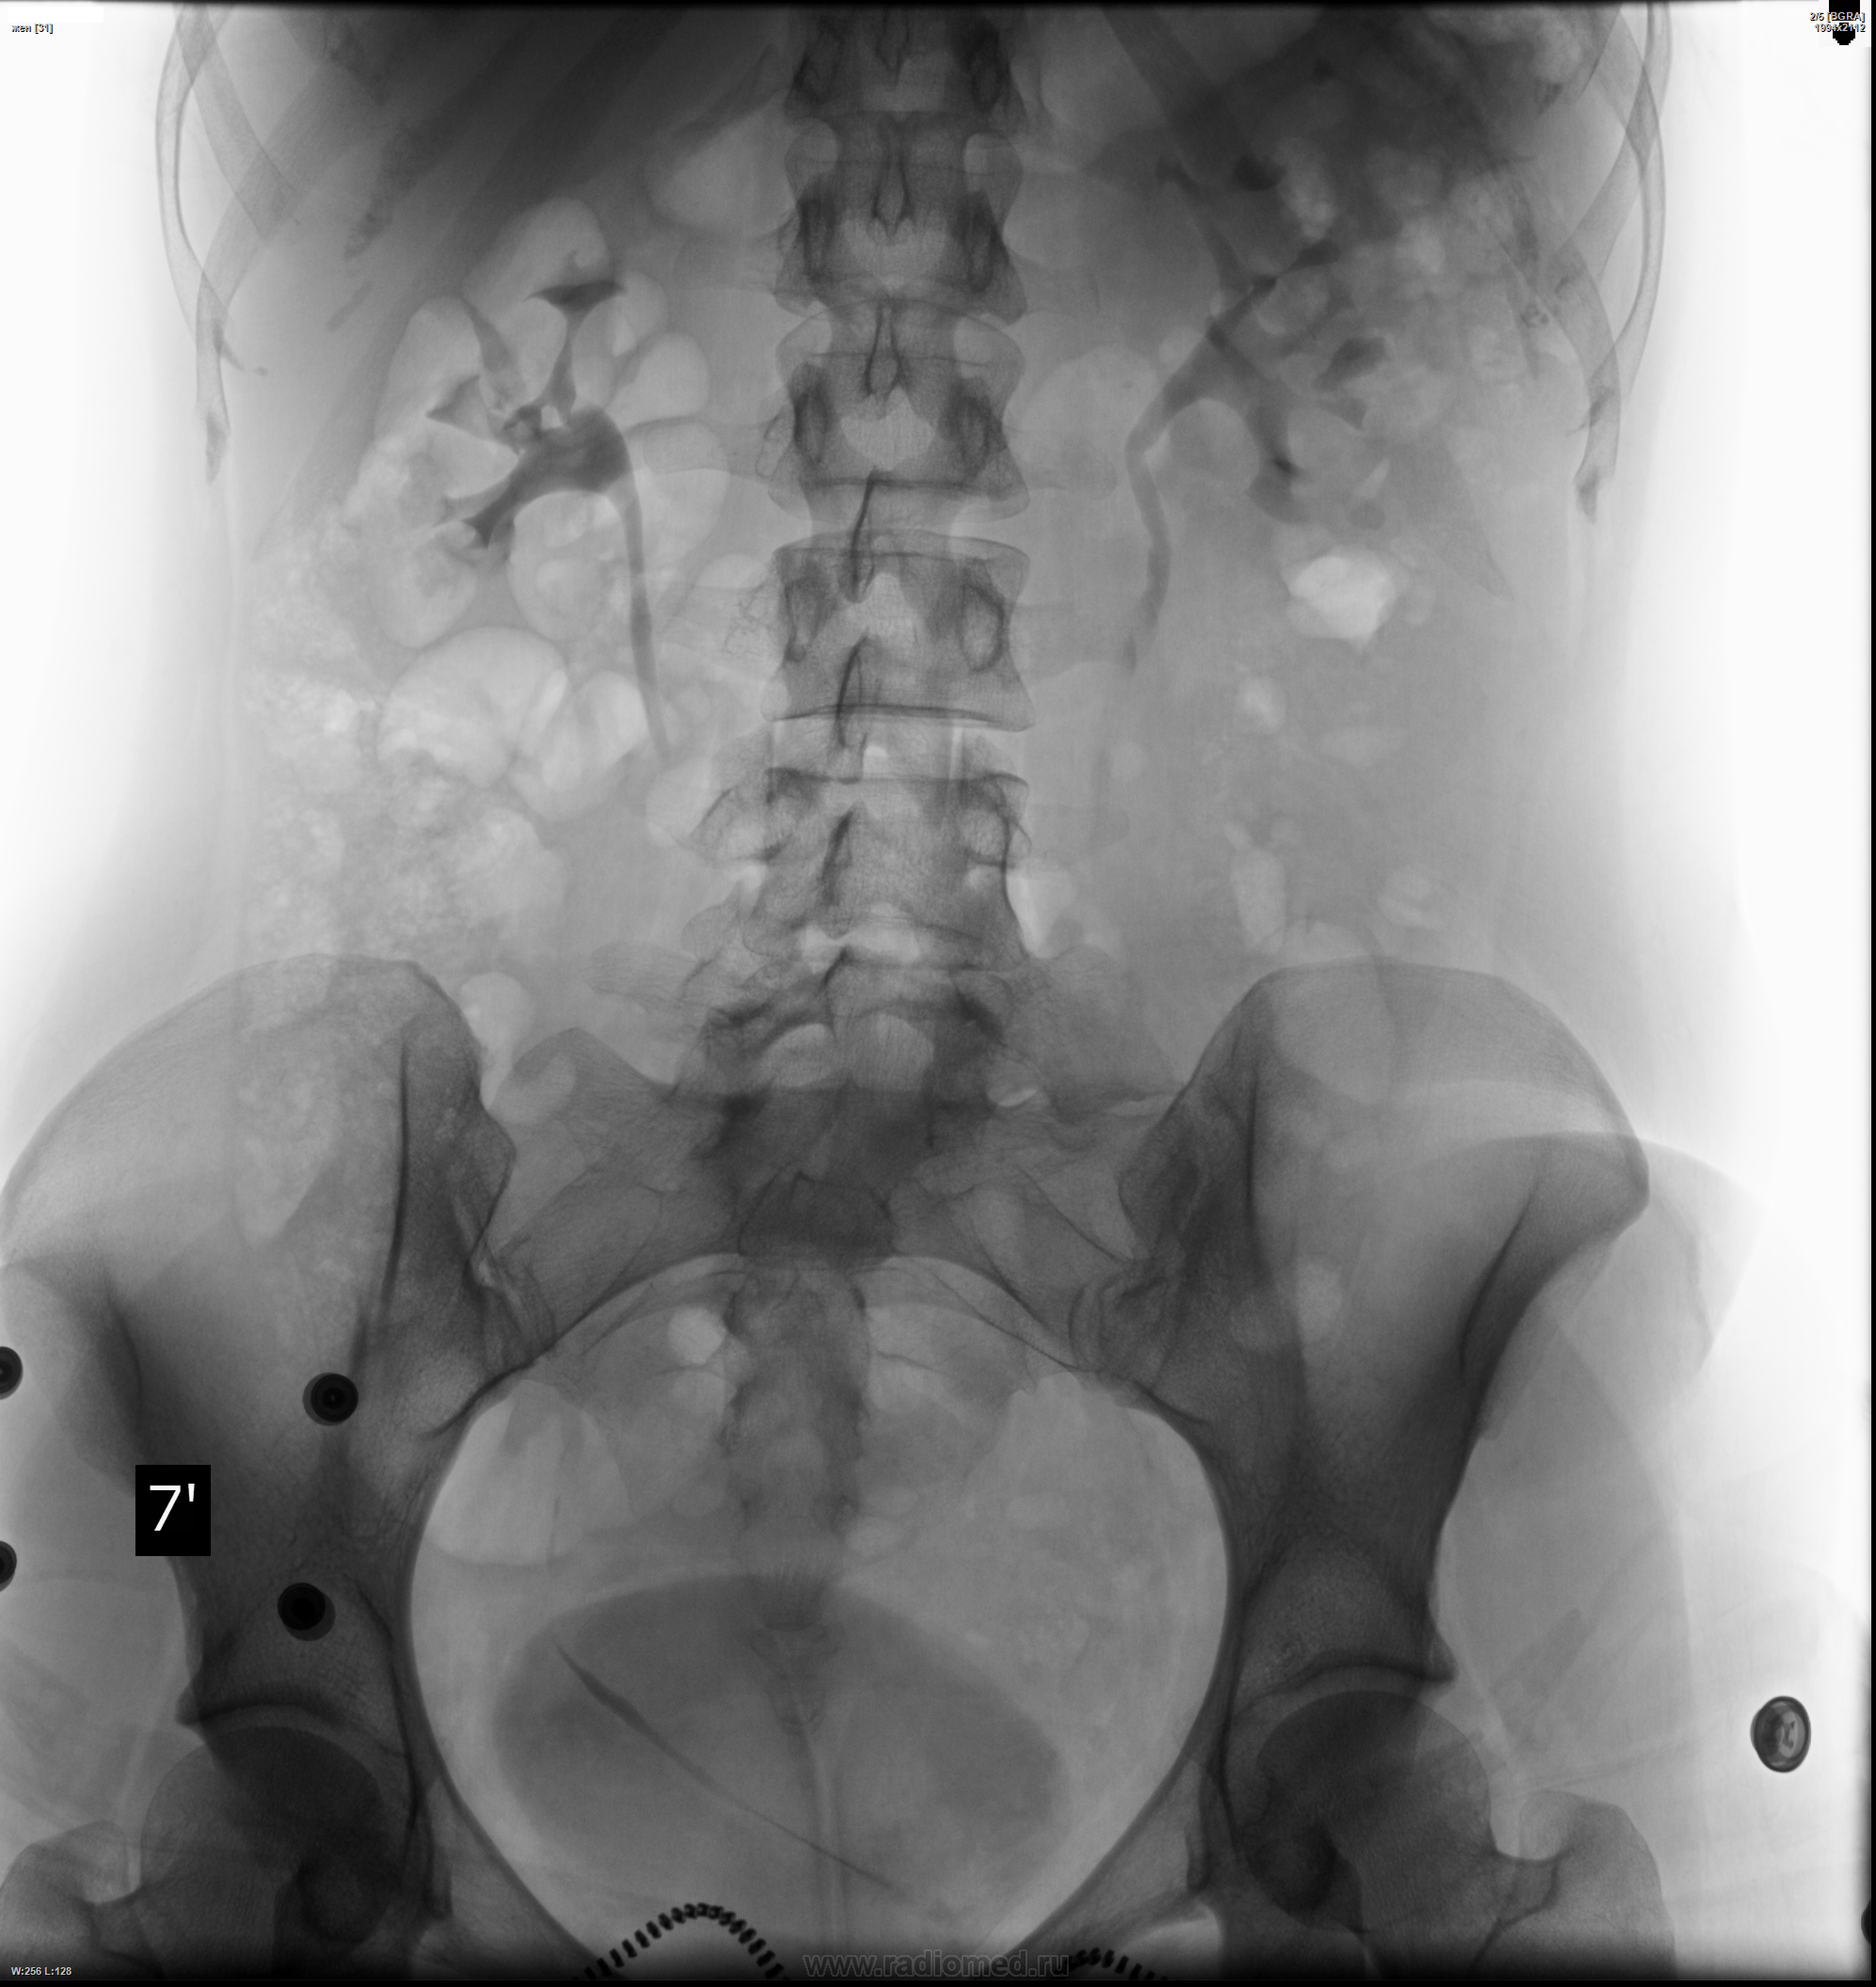

Медицинские изображения: Обзорная рентгенография урография

Раздел: Фокус на знании